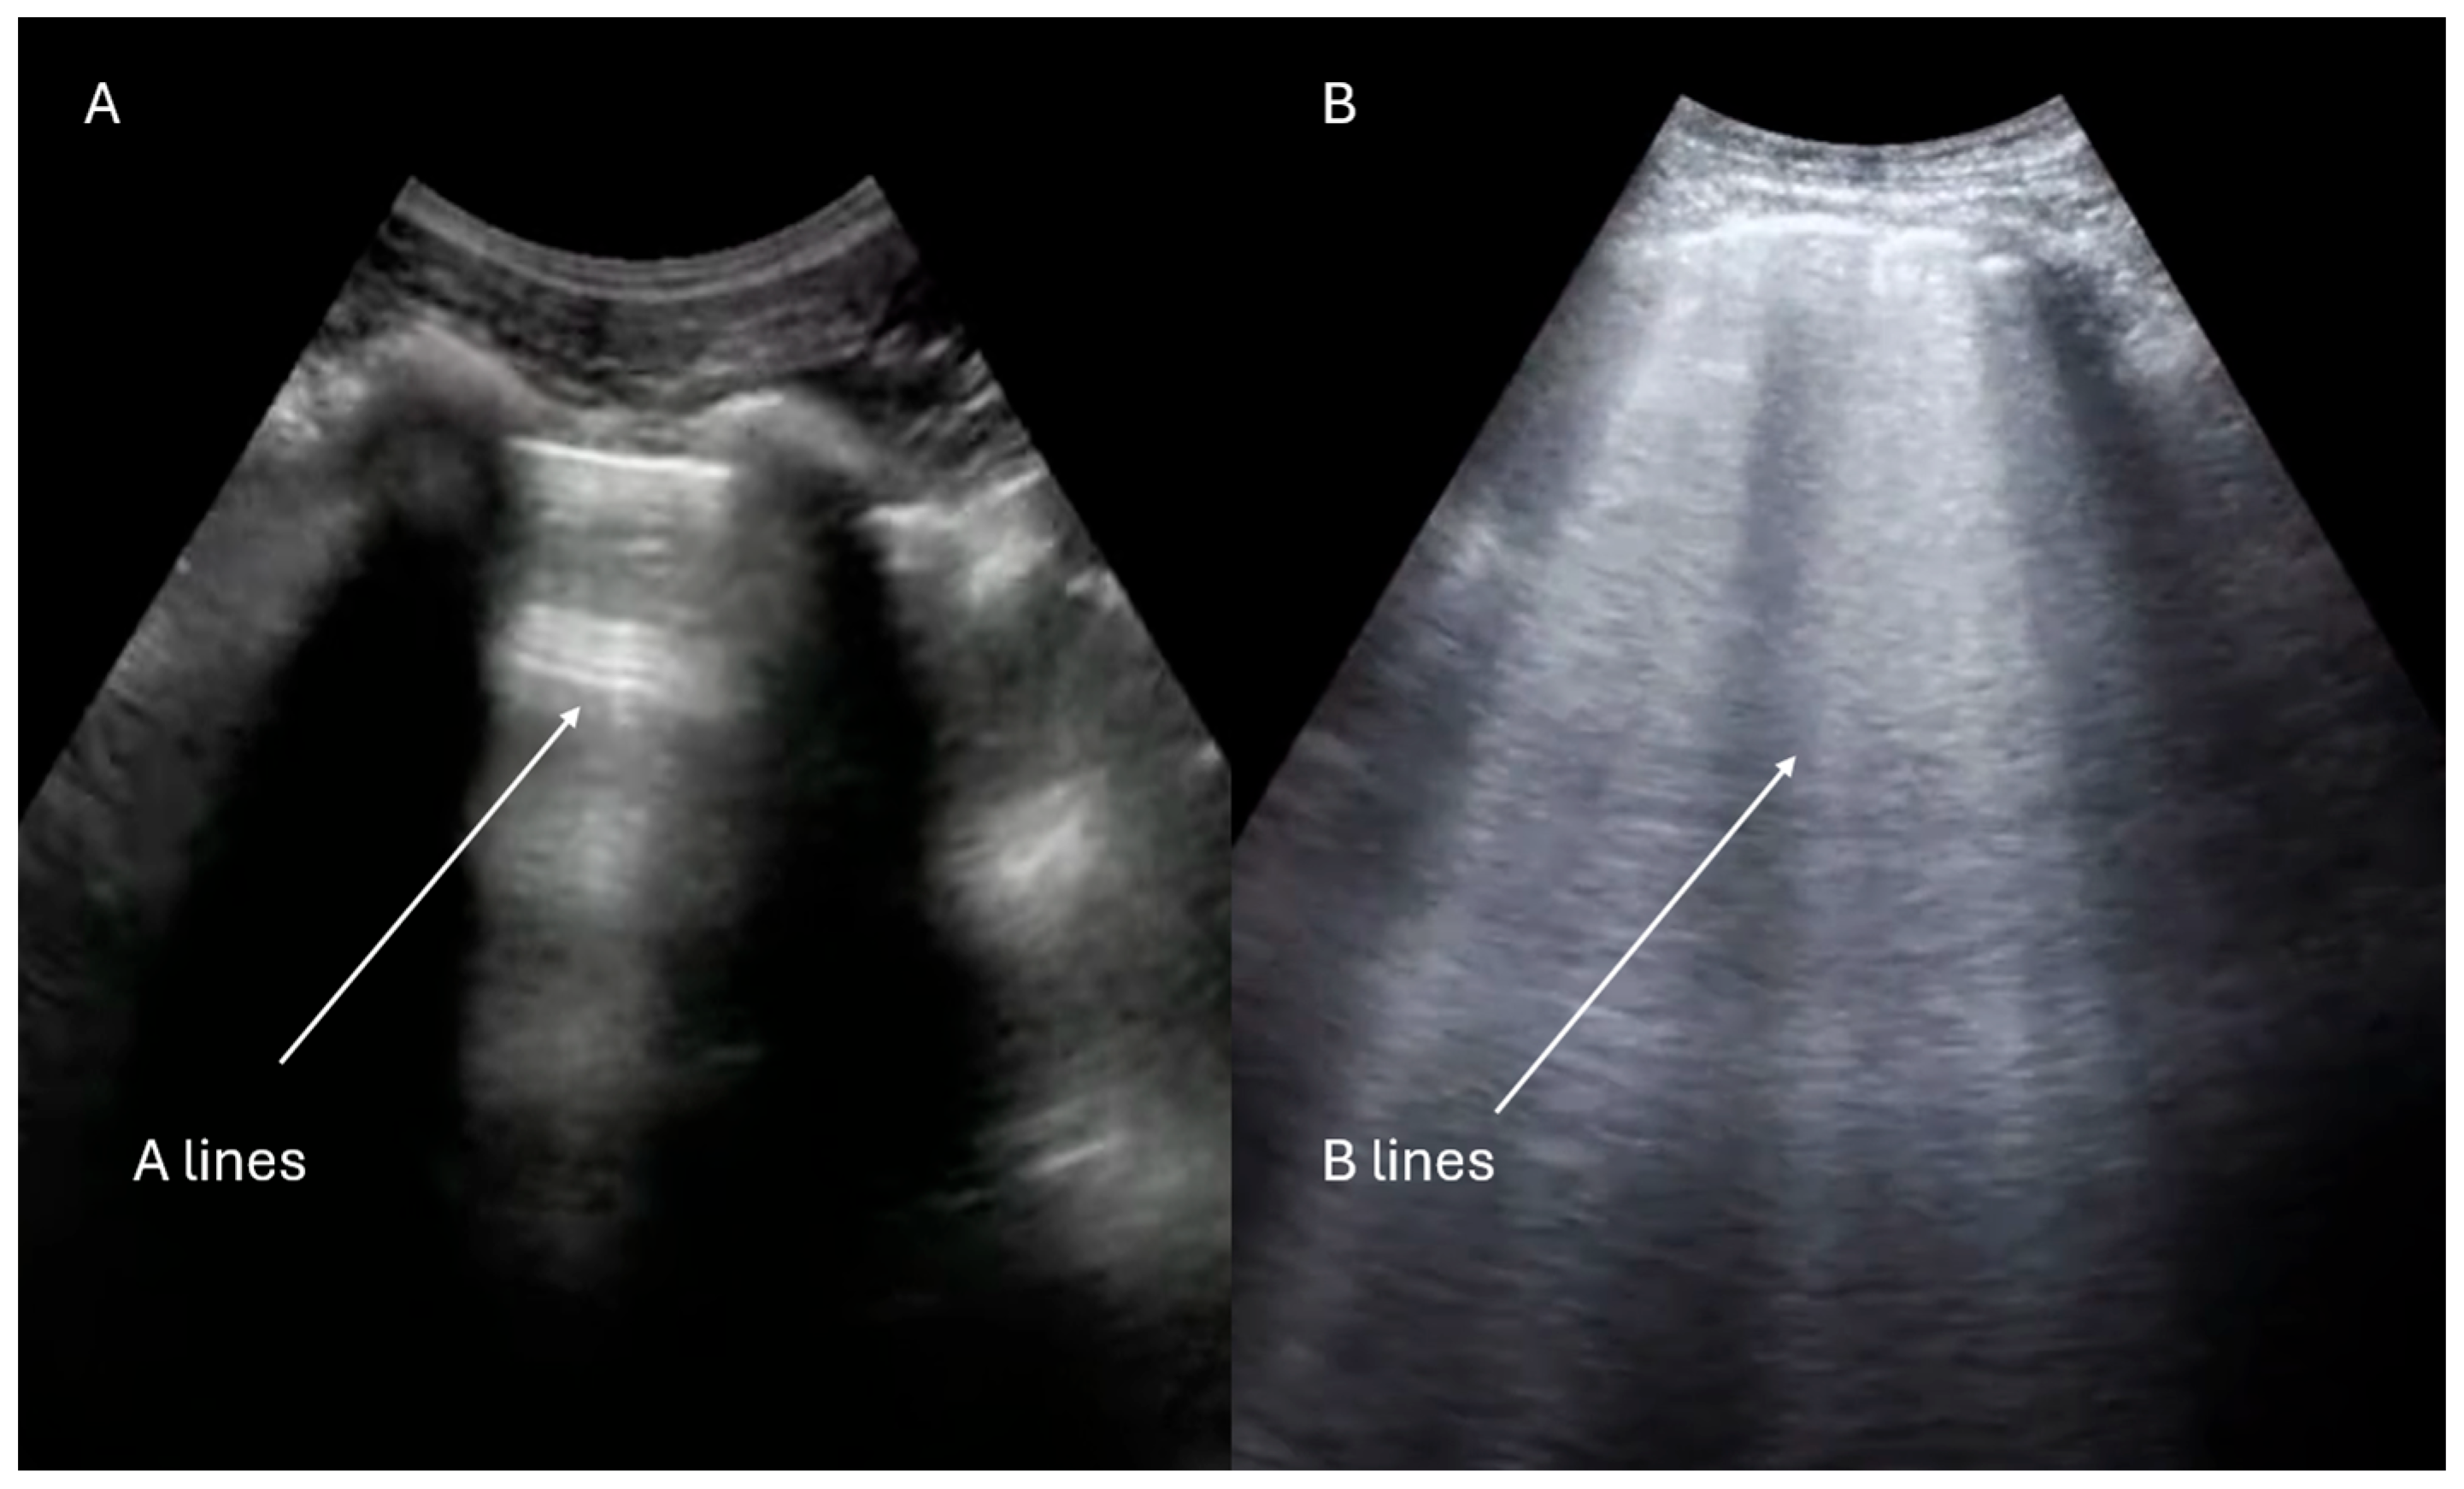

- Lung ultrasound evaluation

- Gargani, L.; Girerd, N.; Platz, E.; Pellicori, P.; Stankovic, I.; Palazzuoli, A.; Pivetta, E.; Miglioranza, M.H.; Soliman-Aboumarie, H.; Agricola, E.; et al. This document was reviewed by members of the 2020–2022 EACVI Scientific Documents Committee. Lung ultrasound in acute and chronic heart failure: A clinical consensus statement of the European Association of Cardiovascular Imaging (EACVI). Eur. Heart J. Cardiovasc. Imaging 2023, 24, 1569–1582. [Google Scholar] [CrossRef] [PubMed]

- Lichtenstein, D.A. Lung ultrasound in the critically ill. Ann. Intensive Care 2014, 4, 1. [Google Scholar] [CrossRef] [PubMed]

- Lichtenstein, D.A.; Mezière, G.A. Relevance of lung ultrasound in the diagnosis of acute respiratory failure: The BLUE protocol. Chest 2008, 134, 117–125. [Google Scholar] [CrossRef]

- Volpicelli, G.; Elbarbary, M.; Blaivas, M.; Lichtenstein, D.A.; Mathis, G.; Kirkpatrick, A.W.; Melniker, L.; Gargani, L.; Noble, V.E.; Via, G.; et al. International Liaison Committee on Lung Ultrasound (ILC-LUS) for International Consensus Conference on Lung Ultrasound (ICC-LUS). International evidence-based recommendations for point-of-care lung ultrasound. Intensive Care Med. 2012, 38, 577–591. [Google Scholar] [CrossRef]

| Lung ultrasound adjunct (B-lines, effusions, PTX signs) | Yes (integrated FoCUS) | Yes (integrated FoCUS) | Optional adjunct |